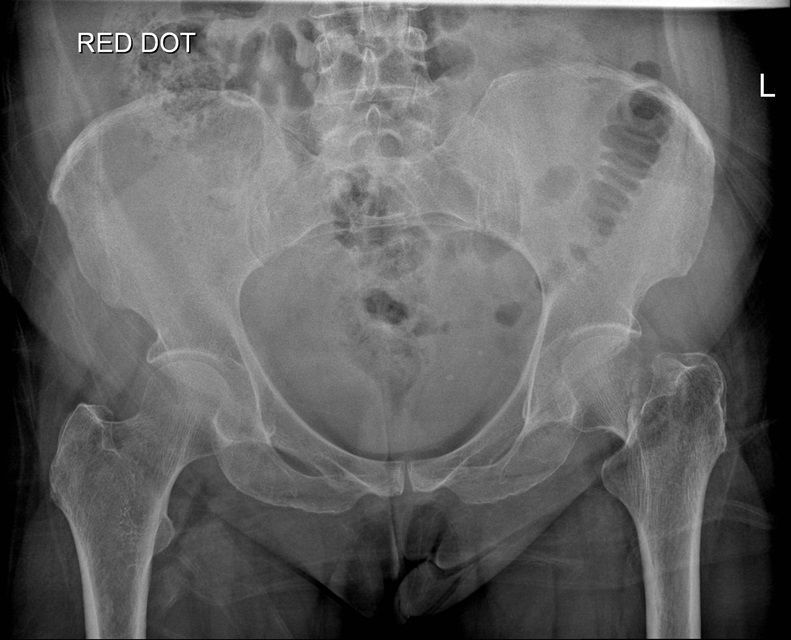

Question 3

Question

Which operation would you perform?

Answer

• THR

• Hemiarthroplasty